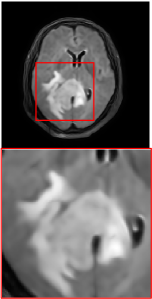

Figure 5 provides the qualitative comparison of the various methods on the four datasets at a scale of 4. The top, second, third, and bottom rows are the SR results under the FastMRI, clinical brain, clinical tumor and clinical pelvic datasets, respectively. The red boxes indicate the zoom-in region of complicated anatomical structures along with their corresponding error maps. Note that the brighter textures in the error maps, the lower the quality of the reconstructed images. As can be seen, compared to methods based on Transformers and CNNs, diffusion-based methods like DisC-Diff and DiffMSR (Ours) are capable of reconstructing high-realistic images with promising reconstruction metric scores (PSNR and SSIM). Nevertheless, while DisC-Diff can reconstruct high-precision MR images, it does not preserve the structure present in the original HR images, introducing some additional information that can affect medical diagnosis. In contrast, our method combines DM and PLWformer, which can preserve the original image’s structure while restoring high-frequency information.

In this section, we present more visual qualitative comparisons. Figures 8, 9, 10, and 11 show the reconstruction results of each method in FastMRI, clinical brain, clinical tumor, and clinical pelvic, respectively. As can be seen, although DisC-Diff can reconstruct MR images with high-frequency information, it fails to preserve the structure and content of the original Target HR image effectively, resulting in image distortion. In contrast, our proposed DiffMSR can restore high-frequency information while preserving the structure of the original HR image, indicating the effectiveness of the joint use of DM and PLWformer.